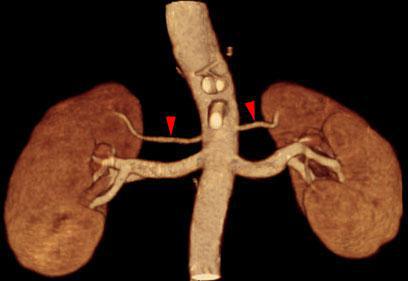

Arterias renales múltiples

Arterias renales accesorias

Arterias renales polares